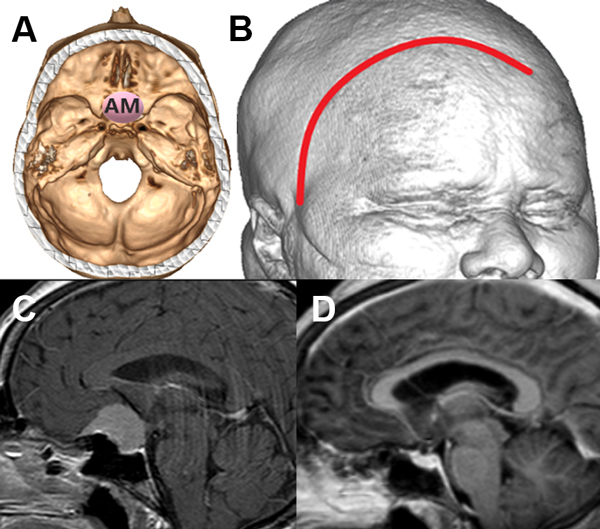

Figura 3: Paciente con meningioma de base de cráneo anteromedial (AM) (1 punto), tamaño menor de 5 cm (1 punto), sin invasión ósea (1 punto), puntaje total: 3, alta probabilidad de resección total. A: localización de lesión en base de cráneo. B: reconstrucción 3D con abordaje. C: resonancia con contraste corte sagital prequirúrgica. D: resonancia con contraste corte sagital posquirúrgica con resección total.